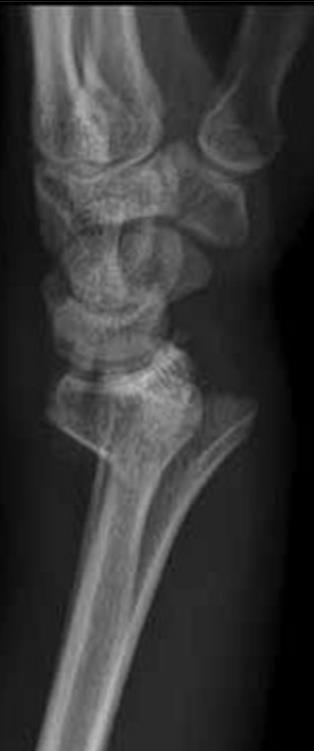

• Smith's fx

• Volarly angulated, extra-articular fx

• comminuted and displaced extra-articular fractures (Smith's fractures)